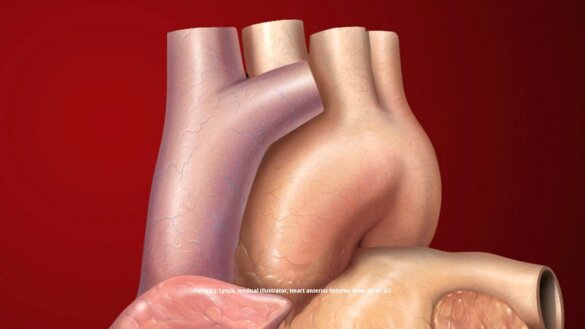

L' aorta e' il vaso sanguigno più grande del corpo umano; origina direttamente dal cuore e si divide in numerosi rami andando ad irrorare tutti gli organi.

L'aneurisma dell’aorta e' una dilatazione pericolosa di un segmento dell' aorta nel suo tratto toracico ascendente. Tipicamente si presenta per un indebolimento della parete aortica che si dilata raggiungendo diametri anche doppi rispetto alla normalità e provocando al tempo stesso la comparsa di insufficienza aortica.